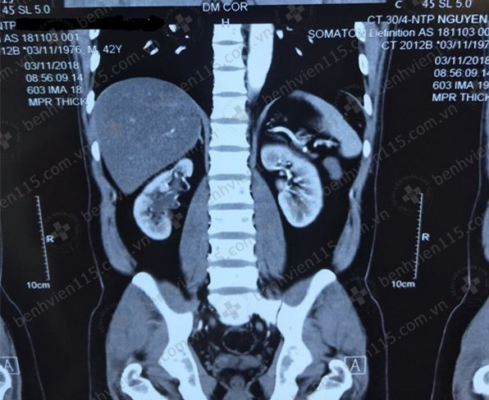

Bà D. đến bệnh viện khám sức khỏe tổng quát, vô tình phát hiện hai quả thận và niệu quản có sỏi lớn gây ứ nước.

Bà Đ.M.D. (65 tuổi, Bình Phước) chia sẻ thỉnh thoảng bà hơi đau tức vùng hông lưng nhưng nghĩ do tuổi cao. Một tháng trước, bà được con gái đưa đến Bệnh viện Đa khoa Tâm Anh TP.HCM khám sức khỏe tổng quát, phát hiện cả hai quả thận và một bên niệu quản có sỏi và đều ứ nước.

Bác sĩ Nguyễn Trường Hoan cho biết có nhiều loại sỏi thận khác nhau, được phân loại theo thành phần hóa học, gồm: sỏi canxi, sỏi oxalat, sỏi phosphat, sỏi axit uric, sỏi san hô, sỏi cystin. Thường gặp nhất là sỏi canxi. Trường hợp sỏi san hô như bà D. chỉ chiếm 7% – 15% số ca sỏi tiết niệu.

Sỏi san hô chỉ xuất hiện trong đài bể thận, hiếm gặp tại cơ quan khác trong hệ tiết niệu. Sỏi hình thành trong môi trường nhiễm khuẩn đường tiết niệu kéo dài, vi khuẩn phân giải urê trong nước tiểu thành ammonium, sau đó kết hợp với magie và phốt phát tạo thành sỏi. Do đó, sỏi san hô còn được gọi là sỏi nhiễm trùng.

Tuy ít gặp nhưng sỏi san hô là loại sỏi nguy hiểm nhất. Người bệnh sỏi san hô thường không có triệu chứng nào nên khi phát hiện, kích thước sỏi đã lớn, lấp kín đài bể thận. Các nhánh sỏi len lỏi vào các đài thận, cản trở nước tiểu di chuyển đến bể thận để đi xuống bàng quang, khiến thận ứ nước tiểu. Nếu không kịp thời lấy sỏi ra ngoài, giải phóng ứ đọng sẽ làm suy giảm chức năng thận, nguy cơ gây nhiễm trùng, ứ mủ trong thận, thậm chí có thể đe dọa tính mạng người bệnh.